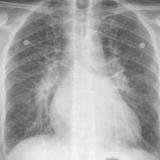

APE 2

Date: 11/05/2005

Views: 2808